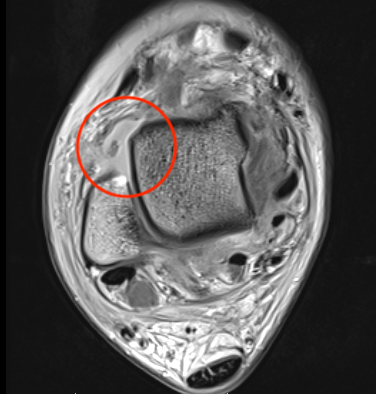

MRI

ATFL normal

Torn ATFL